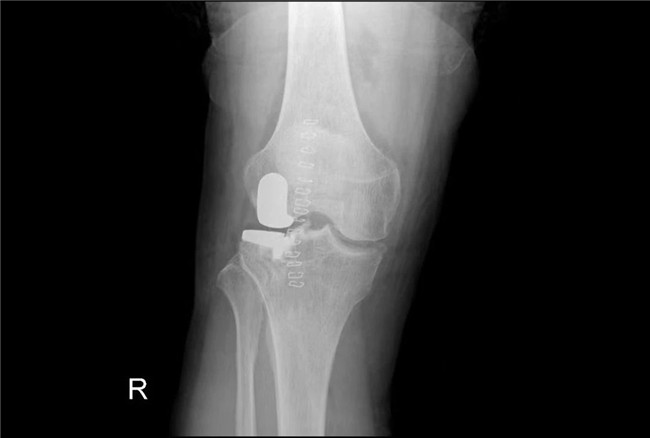

▲術(shù)后假體位置良好,外側(cè)間隙恢復(fù)▲

一個(gè)單髁置換手術(shù)要想達(dá)到理想的手術(shù)治療效果并不簡(jiǎn)單,這與假體的大小、方向和松緊度密切相關(guān),其中任何一點(diǎn)出現(xiàn)差池,結(jié)果都會(huì)差強(qiáng)人意。為此,羅主任團(tuán)隊(duì)在術(shù)前和術(shù)中進(jìn)行了精確的設(shè)計(jì)和測(cè)量,制定周密手術(shù)方案,順利為病人實(shí)施手術(shù),幫助膝關(guān)節(jié)“補(bǔ)牙”。

接診后羅軍主任詳細(xì)檢查病人,發(fā)現(xiàn)病人疼痛癥狀主要集中在膝關(guān)節(jié)外側(cè)間室,右下肢有明顯外翻畸形。這些癥狀都是單髁置換的適應(yīng)癥。雙下肢全長(zhǎng)攝片和右膝內(nèi)翻、外翻位攝片顯示,膝關(guān)節(jié)外側(cè)間隙消失,膝外翻畸形,果不其然印證了上述臨床表現(xiàn)。收治入院后,羅主任團(tuán)隊(duì)決定為患者實(shí)施微創(chuàng)膝關(guān)節(jié)外側(cè)單髁置換術(shù),盡全力為張大爺解除病痛的折磨。